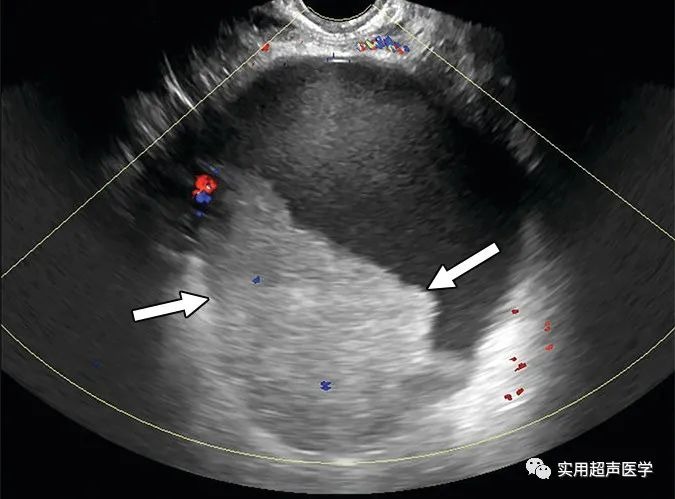

68岁女性腹胀,左卵巢交界性浆液性囊腺瘤。彩色多普勒超声图像显示多房囊肿,内壁和分隔不规则(箭头),无实性成分,符合卵巢-附件报告和数据系统 (O-RADS) 4 类病变。当多房囊肿的内壁或分隔不规则时,代表内部血管和大小的颜色评分 (CS) 无助于 O-RADS 风险评估。